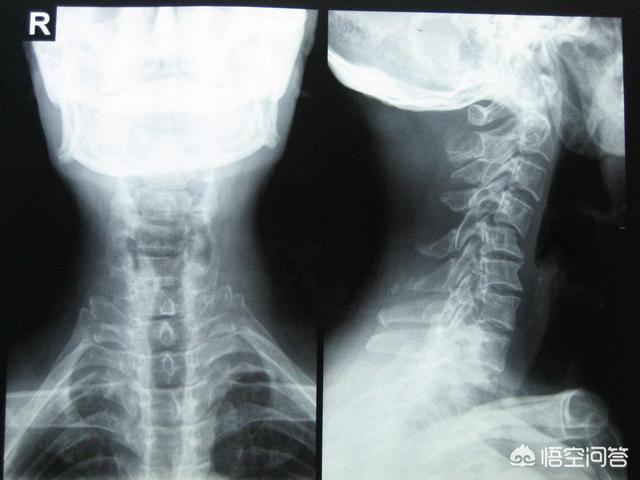

頸椎骨折のようにね。

骨折によって脊柱管内で頸髄が圧迫されると、四肢麻痺を引き起こすだけでなく、それより上(C4以上)の骨折では、脊髄血腫が上方に広がるため、呼吸困難や呼吸循環中枢にまで影響を及ぼすことが多い。

この場合の手術にはリスクが伴うが、それでも医師は患者の命を救う可能性を最大化するためにリスクを取ることを選択することが多い。